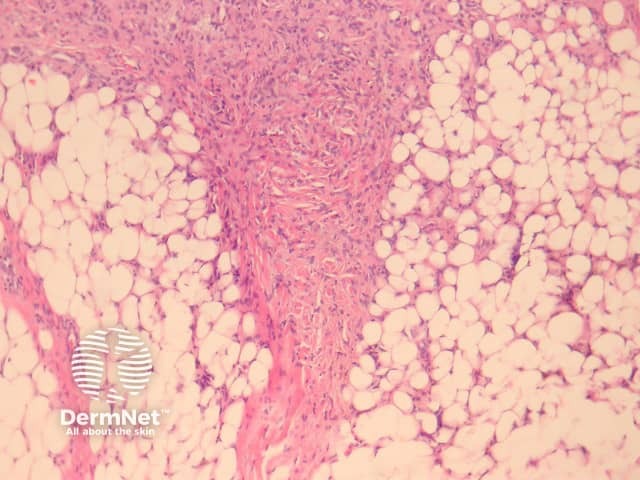

Dermatofibromas are dermal tumours characterised by a poorly defined proliferation of fibrohistiocytic cells within the dermis with an overlying grenz zone of sparing (figure 1). At the periphery of the lesion, there is entrapment of collagen (figure 2). The overlying epidermis may be acanthotic with increased basal layer pigmentation. Sometimes there is basaloid induction of the epidermis (figure 1, arrow) which may resemble small basal cell carcinoma or benign follicular tumours.